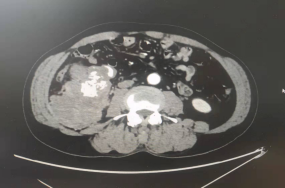

经市七院胃肠肛肠胸外科医生完善检查,江老先生腹部的包块源于他腹中巨大的腹膜后肿瘤!结合CT结果及患者病情,首选的治疗方案是采用手术方式切除肿瘤。然而,如此巨大的腹膜后肿瘤实属罕见,且CT影像提示肿瘤周边血管密布,与下腔静脉、输尿管及肠管紧贴,且肿瘤侵犯腹壁肌肉、髂肌和腰大肌等,术中损伤血管出血的风险极大,手术难度极高。

经术后测量,切除的肿瘤大小约20*18*12cm,重约2.5kg,术中出血量共100ml。术后病理结果提示为恶性梭形细胞肿瘤。